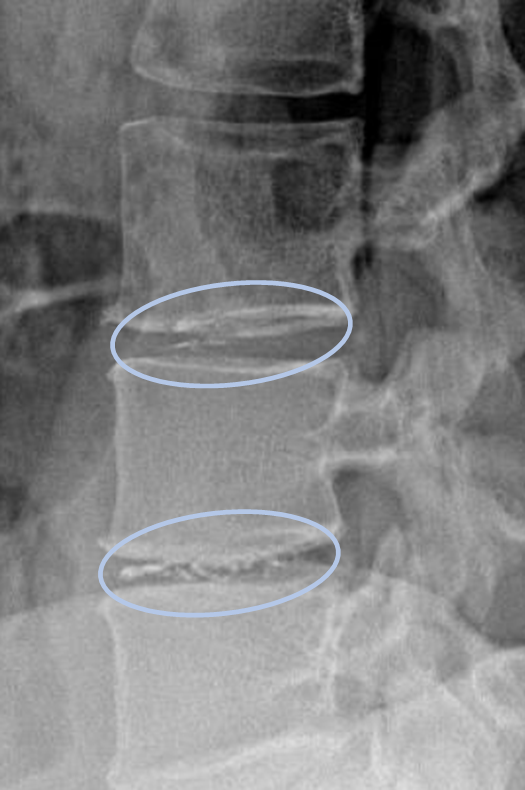

患者様と相談の元、L3/4,4/5にセルゲル法を施行

治療は簑輪院長が行いました。

DiscoGelを入れた後の画像になります。

治療は15分程度で終了

回復室で休憩後、歩いて帰院されました。